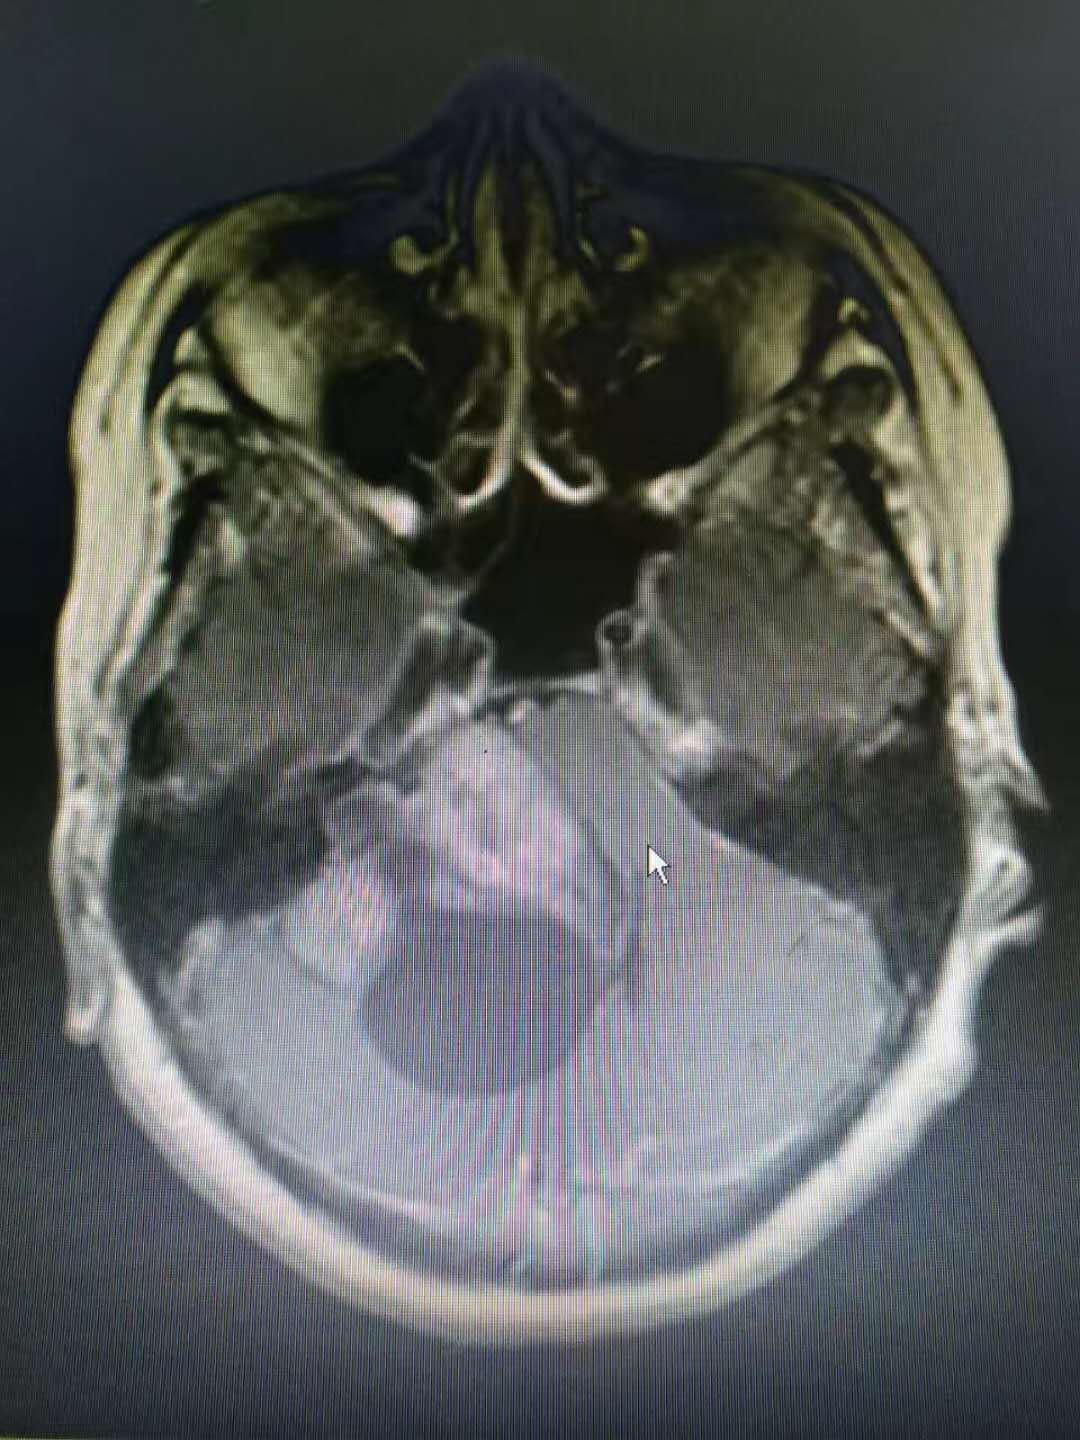

桥小脑角巨大听神经瘤 - 好大夫在线

图片尺寸1440x1080